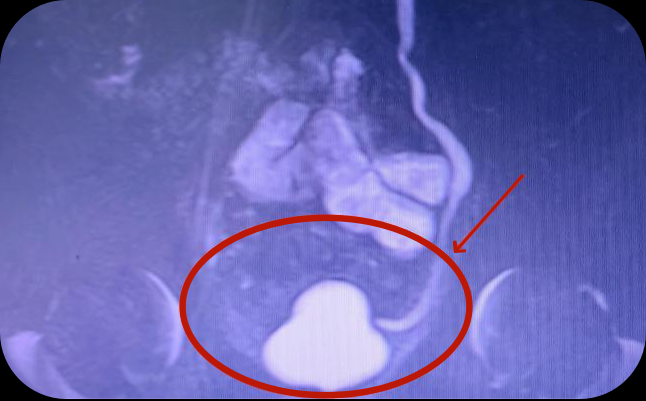

43岁男性患者,因反复尿频2年以上,期间未接受正规诊治,就诊贵州航天医院泌尿外科后,相关检查显示膀胱容量15ml,诊断为泌尿系结核、膀胱挛缩。

2022年底,贵州航天医院泌尿外科就完成了在遵义市首例全腹腔镜下乙状结肠膀胱扩大术,手术效果非常好。当时病例为24岁男性患者,两次排尿间隔仅十几分钟,且每次量很少,反复尿频1年以上就诊贵州航天医院泌尿外科,相关检查显示膀胱最大容量为12ml,被诊断为泌尿系结核、膀胱挛缩。随后,由李凯主刀,实施全腹腔镜下乙状结肠膀胱扩大术,截取肠管缝合成新膀胱,完成患者膀胱扩大术,新膀胱形态正常,无尿漏及其他并发症。

图中标识为术前挛缩的膀胱